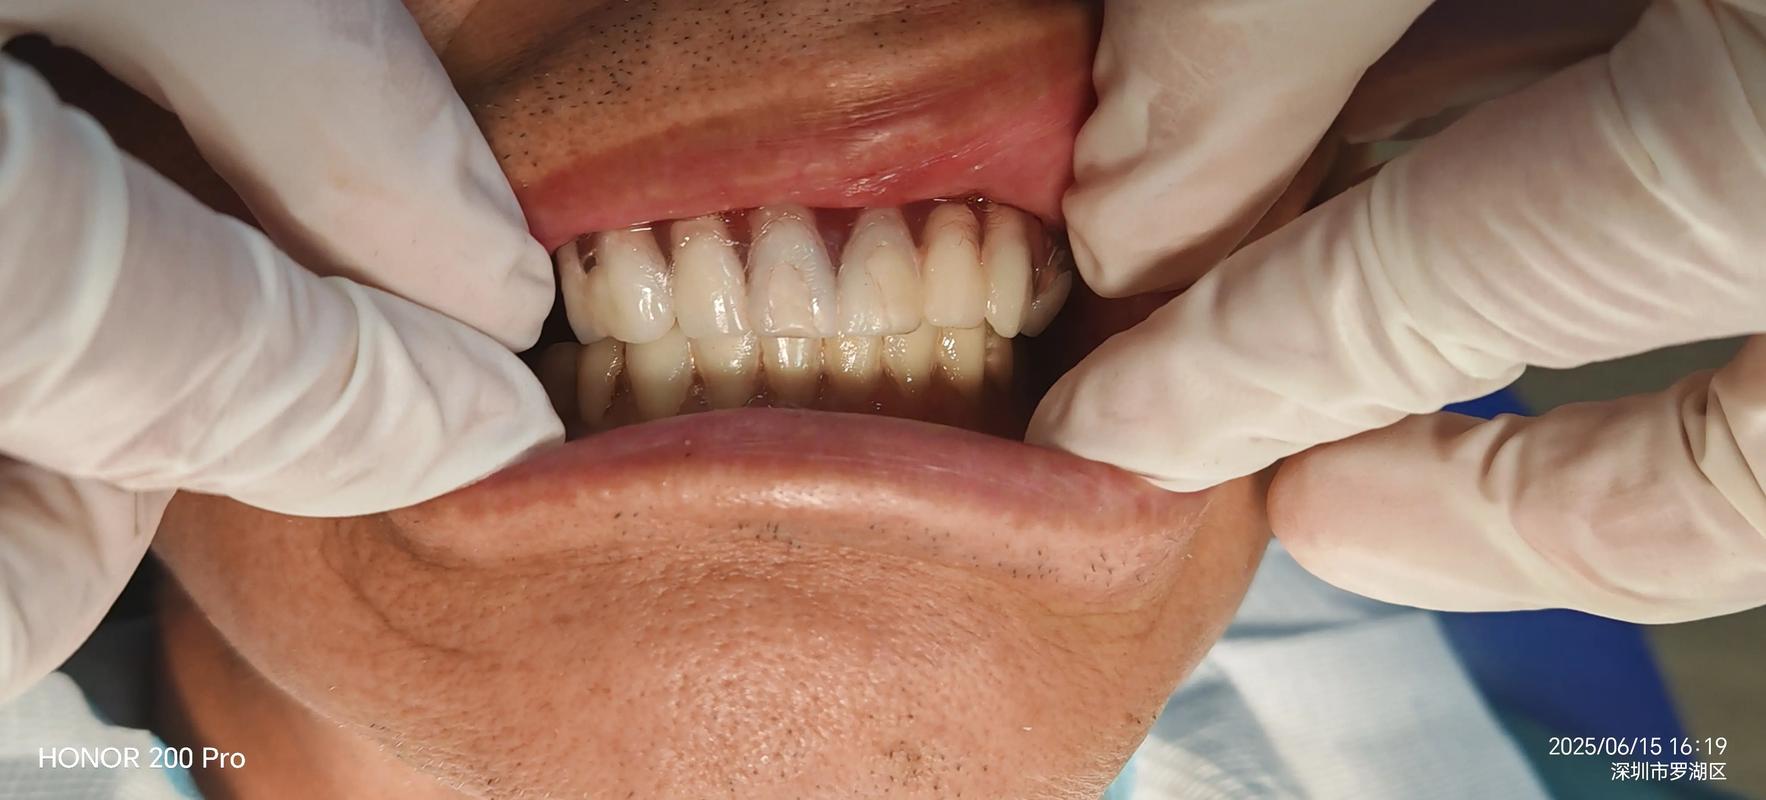

- 医生指导患者:“请慢慢地、自然地咬下去,咬到感觉最舒服、最紧实的地方,保持住,不要动。”

- 患者按照指示,垂直、均匀地咬合,使上下牙齿在蜡片上留下清晰的咬合印迹,咬合的力量应该是患者最大自然咬合力,但不要用蛮力。

- 咬合印迹是否清晰、完整?能否看到上下牙齿的接触点?

- 蜡片是否变形过大或有气泡?

- 咬合关系是否与临床检查一致?